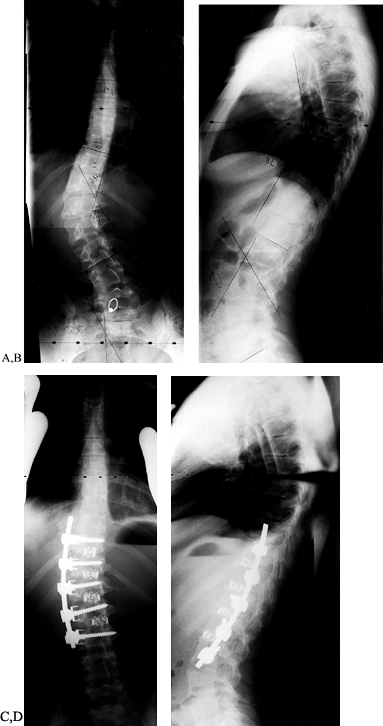

approaching 100% in thoracic-level patients. Nearly 60% of L4 level

require a fusion from T2 to the sacrum (Fig. 155.1).

Figure 155.1. A:

Preoperative AP view of a child with myelomeningocoele and a curve of 58°. A combined anterior release and posterior fusion with Cotrel-Dubousset rods, pedicle screws, and Luque wires was utilized. Postoperative lateral (B) and AP (C) views show excellent correction of coronal and sagittal deformities. A solid fusion is evident at 1-year follow-up. (Courtesy of John Sarwark.) |